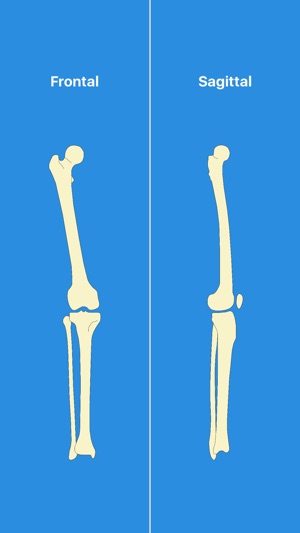

敘述:Measuring tool for lower limb

- Anatomical or mechanical axis in frontal or sagittal plane, ex: MPTA, LDFA, LDTA, PPTA, TBVA, JLCA... etc